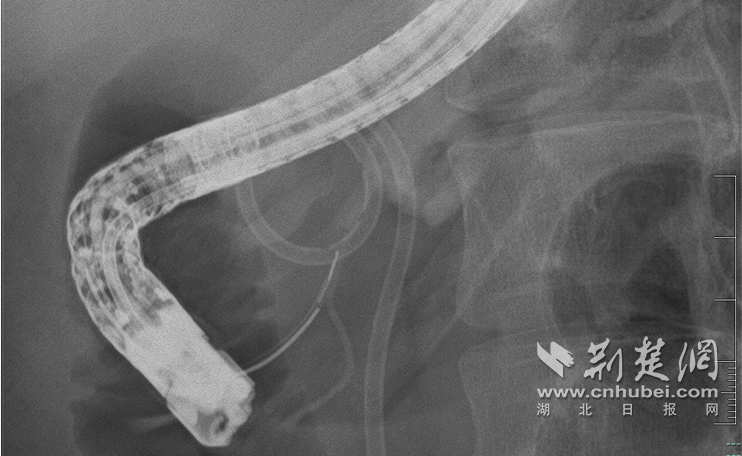

照片显示使用内窥镜对受损胰管进行微创修复。

面对这个问题,大家决定在内窥镜引导下迎接挑战并最小限度地修复破裂的胰管。 10月30日的术中血管造影清楚地显示了病情的复杂性。胰头胰管扭曲,胰管颈部完全堵塞,形成直径约2厘米的囊肿,远端胰体及胰管尾部因阻塞而明显扩张。

技术难点在于空间定位。在医疗队员的密切配合下,覃华和副主任医师罗振龙在X光引导下小心翼翼地将导丝穿入囊腔,精准定位细如发丝的破裂远端胰管末端的开口,实现了破裂胰管的“胜利遭遇”。专家随后成功插入支架并重建胰腺引流通道。目前,秀英正在康复中身体很好,可以正常吃饭。